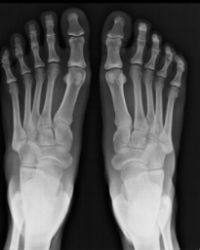

SPECIALTY X-RAY MACHINES

We have a special X-Ray machine that allows us to perform “weight bearing” X-Rays or “standing” X-Rays of the foot and ankle right in the office. Weight bearing X-Rays are very important in accessing the true structure of your foot. The typical X-Ray machine used by hospitals and large clinics don’t have the ability to take a true “weight bearing” X-Ray.